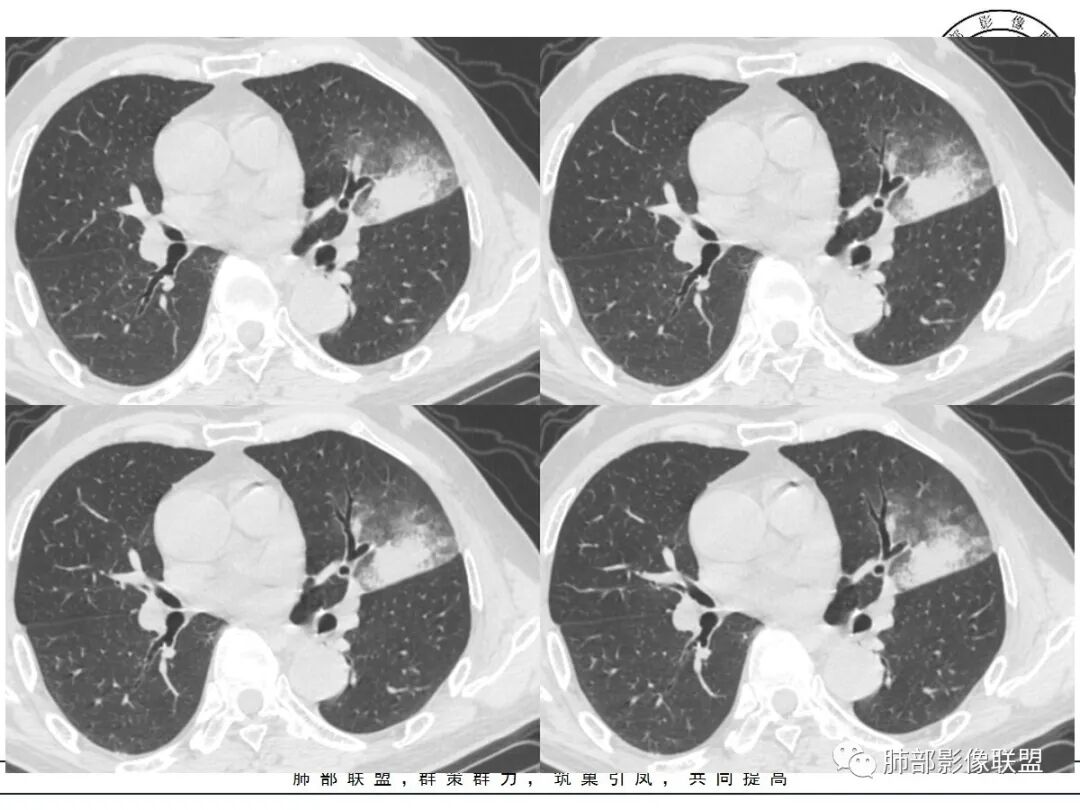

左肺上叶类圆形软组织影,边界较清楚,其内密度均匀,外侧缘可见空气新月征,并可见点状钙化,增强扫描可见均匀强化,病灶周围可见磨玻璃渗出性密度影,斜裂侧光滑平整。考虑炎性病灶,以肉芽肿性炎症为主(如真菌性肉芽肿),鉴别结核(无卫星灶,无多态性),肺癌(无毛刺,分叶等恶性征象,)细菌性炎症(密度一般不这么致密,很少钙化及空气新月征)。

左肺上叶类圆形软组织影,界清,内见空洞影,病灶周围斑片影,可见空气支气管征,未垮叶。考虑炎性病变,糖尿病四大金刚,肺克?毛霉?

老年男性,血糖升高六年,反复咳痰咳嗽3周,左肺上叶近斜裂类圆形肿块影,边缘伴磨玻璃影,边界不清。内部可见支气管走行、钙化、小空洞,叶间裂局部膨隆,增强扫描轻度强化,内部可见小的低密度区,边界尚清。考虑为炎性病变可能性大。

左肺叶裂旁实变影,宽基底与叶裂胸膜相连,边缘平直,部分略膨隆,病灶近段及上段支气管深入病灶内,部分壁略增厚,远端支气管截断,似有小空泡,壁规则,内部可见高密度钙化,周围可见模糊的GGO,血象正常,考虑结核(NTM),鉴别隐球菌,奴卡,放线菌。

老年男性,66,反复咳嗽、咳痰3月。糖尿病,血象不高。

胸部CT:左肺上叶类圆形肿块影,边界较清楚,密度较均匀,内可见小片坏死、偏心空洞、空气新月征、点状钙化,周围晕、絮状渗出、边缘模糊,支气管扩张、充气征、支气管进入病灶堵塞,叶裂牵拉明显,增强扫描中度均匀强化,纵隔可见淋巴结。考虑:炎性病灶,肉芽肿性炎症,曲霉?毛霉?鉴别:TB,淋巴瘤。

左上肺类圆形肿块影,边界较清楚,支气管通畅略扩张,周围磨玻璃影,其内密度均匀,外侧见空气新月征,且见点状钙化。叶间裂光滑稍膨隆。老年男性,糖尿病,高血压,痰培养克雷伯菌。综合考虑炎性病灶,克雷伯合并真菌感染,曲霉。结核合并真菌。鉴别肺癌合并感染。

左肺上叶类圆形软组织影,边界稍模糊,其内密度均匀,外侧缘可见空气新月征,并可见点状钙化,增强扫描渐进性强化,病灶周围可见磨玻璃影,斜裂侧光滑平整,气管未见明显闭塞,淋巴结未见肿大,糖尿病患者,首先考虑感染性变,结核并曲霉?